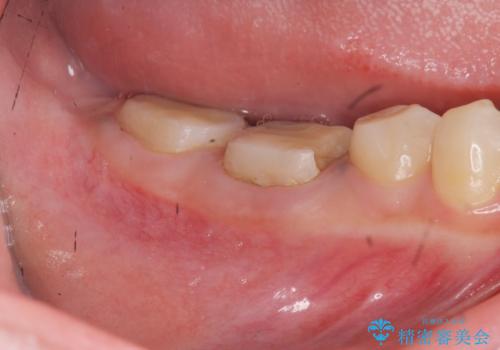

治療途中で長期間放置していたため、歯が歯ぐきから挺出(伸びてくる)してしまい、十分に強度を担保できるセラミッククラウンを装着するスペースが不足した状態です。

加えて、舌の邪魔になっている骨隆起や根尖病変といった問題を歯周外科・精密根管治療を行い、しっかりとスペースを確保したのちセラミッククラウンを作製していきます。